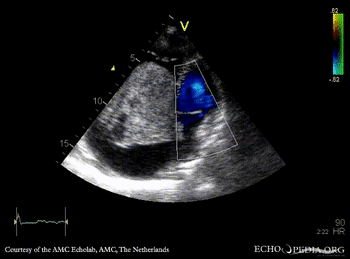

| Giant myxoma in right atrium

| PLAX: giant mobile myxoma in right atrium

A4CH

| Subcostal view